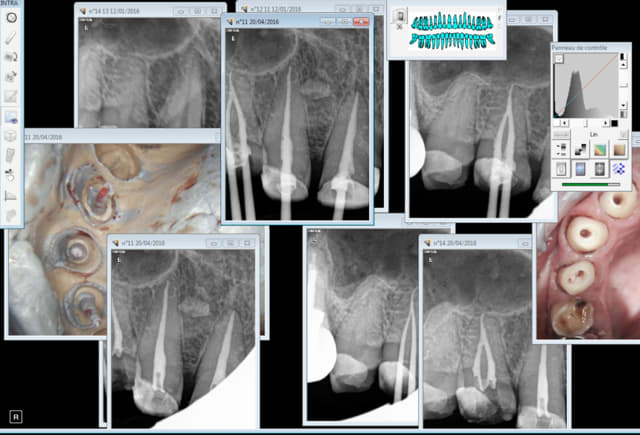

Je précise soins opposables hors endo ( j'adore l'endo) . Comme dans ce cas ou j'étais parfaitement détendu. -)

Capture d e cran 2016 04 20 10.52 - Eugenol

Faire ca en 30 mn sans assistante au fauteuil alors qu'on a prévu une heure ca détend. -)

Capture d e cran 2016 04 20 11.56 - Eugenol